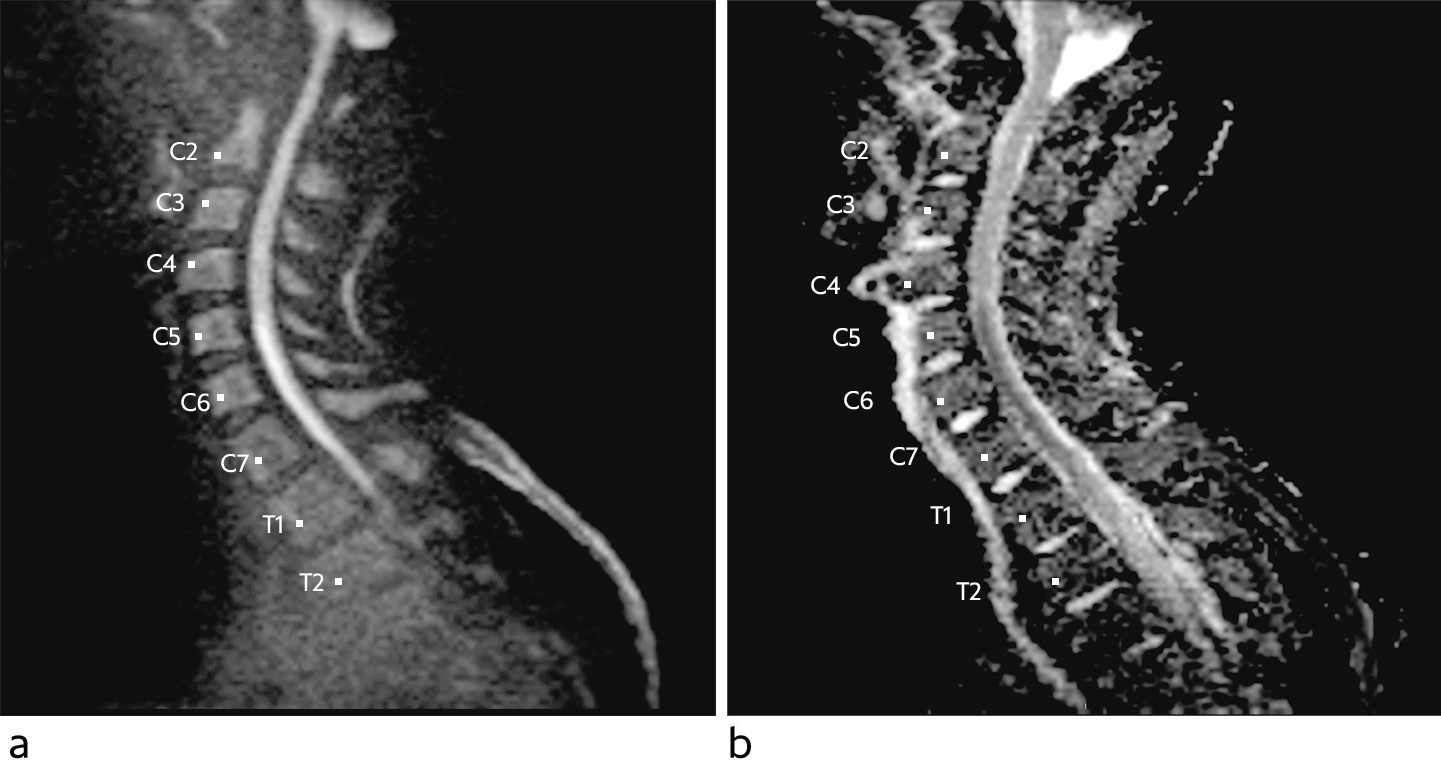

The MRI revealed increased DWI signal and reduced ADC values in the ventral part of the spinal cord from level C5 through Th1, extending almost 7 cm (Fig. 1). The spinal cord was not swollen, and no contrast enhancement was detected. An axial image (Fig. 2) at the same levels showed increased T2 signal in the anterior horn bilaterally, so-called snake-eye appearance, consistent with one of the known patterns of ischaemia in the area supplied by the anterior spinal artery. Findings of restricted diffusion with "vascular distribution" aroused suspicion of cytotoxic oedema due to acute ischemia. At this point there was no evidence of infection, as the patient was afebrile and had normal blood test results. Inflammation was still a possible differential diagnosis. There were no signal alterations and no evidence of infarction or other pathology in the cervical vertebral bodies, but somewhat dehydrated discs. Later the same day a CT angiogram of the aorta was performed, which did not reveal dissection, aneurisms or any other source of embolism.

Figure 1 Sagittal diffusion-weighted MRI sequence with b-1 000 image (a) and apparent diffusion coefficient (ADC) map (b)…

Figure 1 Sagittal diffusion-weighted MRI sequence with b-1 000 image (a) and apparent diffusion coefficient (ADC) map (b) shows diffusion restrictions in the ventral part of the spinal cord from the level of C5 to Th1, consistent with cytotoxic oedema.